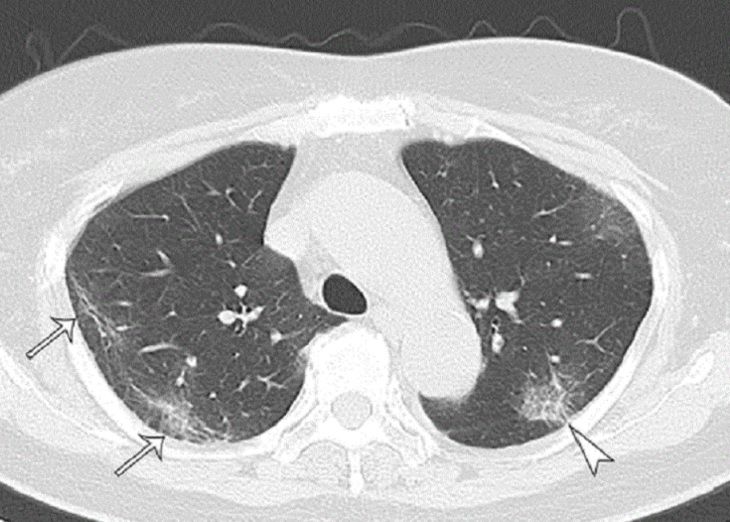

У большей части бессимптомников по результатам КТ произошли деформации в легких — «эффект матового стекла».

Таким образом, японские ученые сделали вывод, что легкие бессимптомников страдают не меньше, нежели у тех, кто переболел.

Фото: pubs.rsna.org